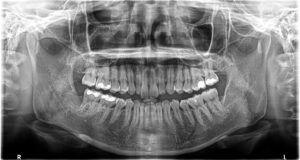

抜歯後レントゲン。左右ともに根の先まで抜けました。